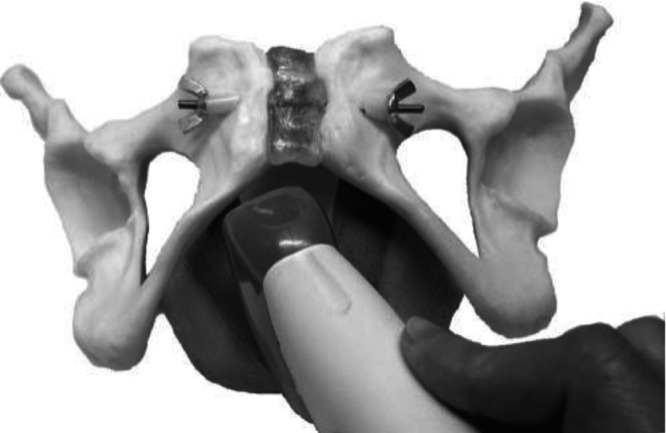

Methods: This was a cross-sectional prospective study of women attending a tertiary urogynecological service between February 2021 and August 2022. All women underwent a standardized interview, pelvic organ prolapse quantification (POP-Q) assessment and four-dimensional transperineal ultrasound. 2D oblique parasagittal ultrasound imaging was performed by rotating the transducer 10-20° from the midline to line up the main transducer axis with the fiber direction of the puborectalis muscle, followed by a full parasagittal sweep of the hiatus at rest. Postprocessing of archived ultrasound volume data was performed at a later date, blinded to all other data. Findings were compared with levator ani assessment results obtained previously using three-dimensional tomographic ultrasound imaging (TUI). Diagnosis of levator ani avulsion on TUI and oblique parasagittal imaging was analyzed for associations with pelvic organ prolapse (POP).